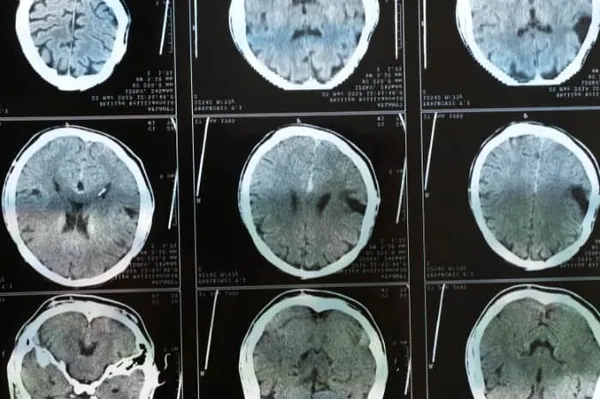

A cinquant’anni dalla prima pubblicazione della Glasgow Coma Scale (GCS) ideata da Teasdale e Jennet nel luglio 1974, la scala pratica per la valutazione del coma e della coscienza alterata ha superato la prova del tempo restando un valido indicatore di gravità clinica ed un efficace strumento quoti